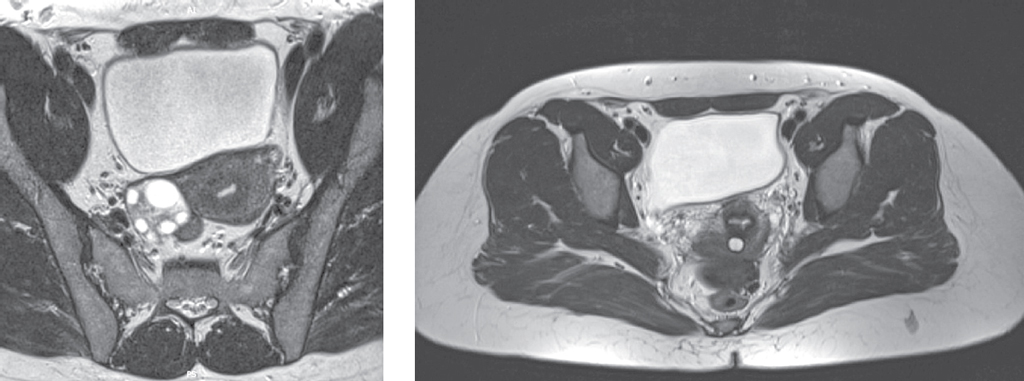

В анамнезе в 2012 г. на сроке беременности 5/6 нед. отмечала внезапно возникшую на фоне полного благополучия постоянную сильную боль внизу живота. При ультразвуковом исследовании органов малого таза патологии не выявлено. Постоянный прием нестероидных противовоспалительных средств в течение 2 нед. (нурофен, баралгин) периодически незначительно уменьшал болевой синдром. Тошноту, рвоту отрицает. На сроке беременности 7/8 нед. — вакуум-аспирация содержимого полости матки. Болевой синдром прекратился. Через год внезапно появление интенсивной непрерывной боли в течение нескольких дней, обследована — патологии не выявлено. Болевой синдром связывали с радикулопатией. В июне 2021 г. при плановом обследовании по ультразвуковому исследованию органов малого таза левый яичник не визуализируется. В позадиматочном пространстве определяется овальной формы образование неоднородной структуры (гипоэхогенное с гиперэхогенными включениями), без кровотока при цветовом доплеровское картировании, размерами 38 × 18 × 25 мм. По данным магнитно-резонансной томографии органов малого таза от октября 2021 г.: признаки кистозного образования в позадиматочном пространстве с геморрагическим или высокобелковым содержимым — вероятно, эндометриоидная киста позадиматоного пространства. Левый яичник убедительно не определяется (рис. 1).

Рис. 1. Магнитно-резонансная томография органов малого таза / Fig. 1. Magnetic resonance imaging of pelvic organs